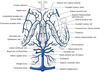

Describe the intracranial course of the carotid artery

Enters the skull in the middle cranial fossa beside the dorsum sellae of the sphenoid.

Carotid siphon- anterior, superior at medial ACP, enters subarachnoid space and courses posteriorly below optic nerve turning upwards lateral to optic chiasm

Divides into terminal branches below anterior perforated substance

Passage of the anterior choroidal artery

Posterior- along optic tract, choroid fissue at medial edge of temporal lobe

Branches to optic tract, uncus, amygdala, hippocampus, globus pallidus, lateral geniculate body and ventral part of the internal capsule.

Terminal branches→ choroid plexus in temporal horn anastomosing with posterior choroidal

Passage of MCA

Runs deep in the lateral sulcus between the frontal and temporal lobes

Branches of the ACA

Ascends in the longitudinal fissure and bends backwards around the genu of the corpus callosum.

Supplies medial part of the orbital sufrace of frontal lobe including the olfactory bulb and tract.

Continues along the upper surface of the corpus callosum as the pericallosal artery and a large branch, the callosmarginal artery follows the cingulate sulcus.

How does the vertebral artery enter the subarachnoid sapce?

Pierces the atlanto-occpital membrane then the arachnoid and dura mater at the foramen magenum

Passage of PICA

Irregular course between medulla and cerebellum.

Branches of PICA

Distributed to posterior parts of the cerebellar hemisphere, inferior vermis, central nuclei of cerebellum and choroid plexus of the fourth ventricle.

There are also important medullary branches to the dorsolateral medulla